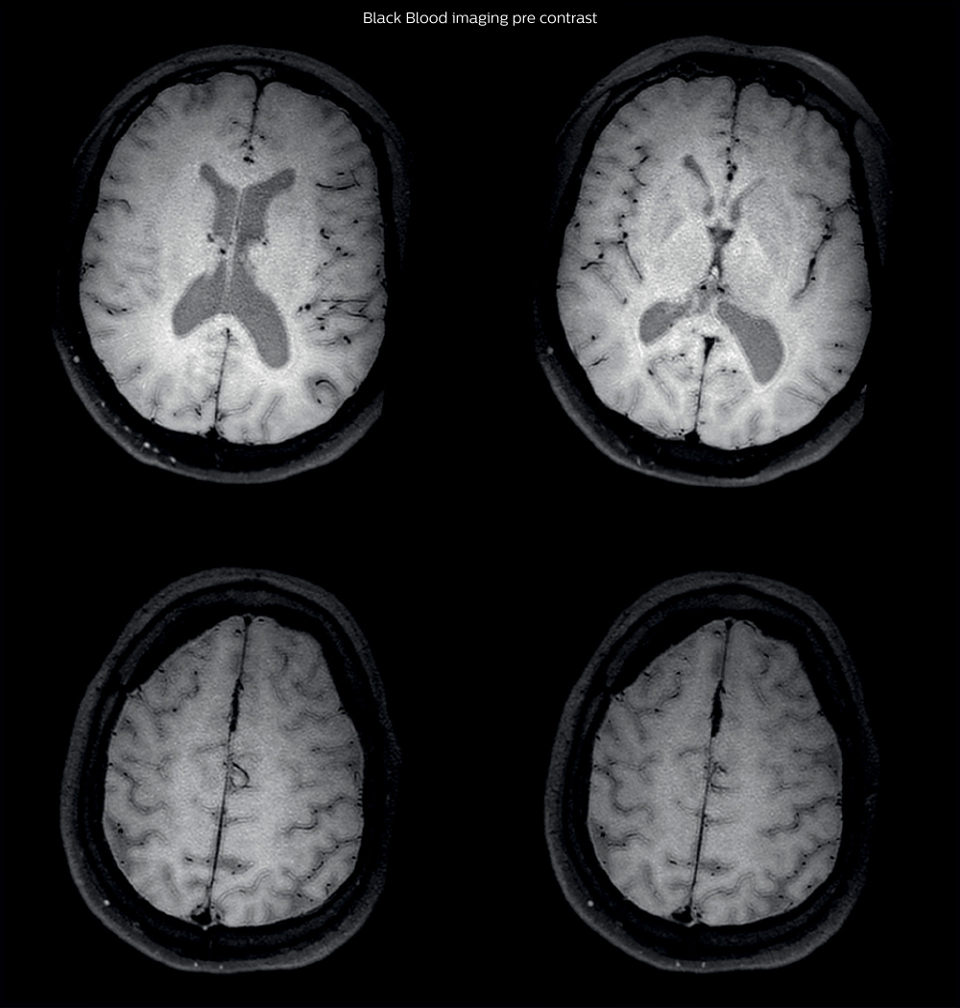

After a conventional routine MR imaging examination, the suspicion of vasculitis arose, therefore we performed an MRI including Black Blood imaging in a separate session. The dedicated ExamCard includes diffusion, FLAIR, MR angiography

using TOF, and 3D T1 MRA with bolus injection. This ExamCard also includes Black Blood imaging before and after contrast. This examination was performed on our Ingenia 3.0T. Black Blood scan time 4:39 min, acquired voxel size 0.75 x 0.75 x 1.0 mm, 21 slices.

On FLAIR images we can see some nonspecific high signal abnormalities in frontal white matter bilaterally. On DWI we can see acute ischemic lesions which appear with high signal intensity. Arrows show vessel wall enhancement which appears concentric and homogeneous in different cerebral territories.

Black Blood Imaging Case 1 B Pre contrast1